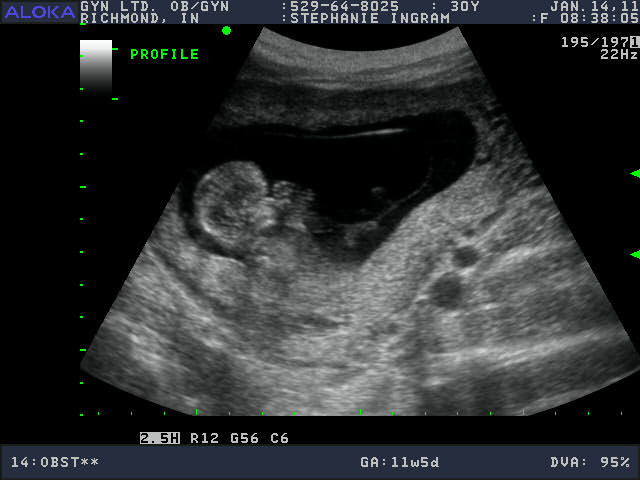

Pictures make it all so real doesn't it! Here it is with its hands up by its face

During the ultrasound the baby had its feet up in the air the whole time. I was amazed that at even this early in the process I could see the details of its toes and fingers. Its cute huh!

Hahaha. Kicking and Swatting already. Watch out Grant.... this ones gonna come and get ya! The ultrasound tech said that there is a somewhat new hypothesis that even though you cant see if its a boy or girl at this stage that there are developmental features that literally point one way or the other. She has been trying out the hypothesis and she has been right 5/7 times. Not exact but fun either way. She said girl.... which confirms what I have been feeling all along. We shall see! :)